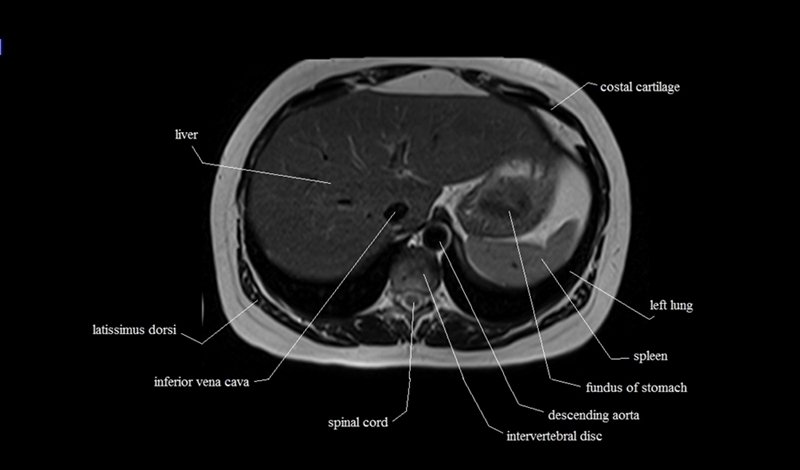

MRI Axial Cross Sectional Anatomy of Chest

This MRI chest (thorax) axial cross sectional anatomy tool is absolutely free to use. Use the mouse scroll wheel to move the images up and down, or alternatively, use the tiny arrows (→) on both sides of the image to navigate through the images. For a more detailed view, double-click the image to view it in full screen, and use the menu in the top right-hand corner to view individual slides or play them in a loop.